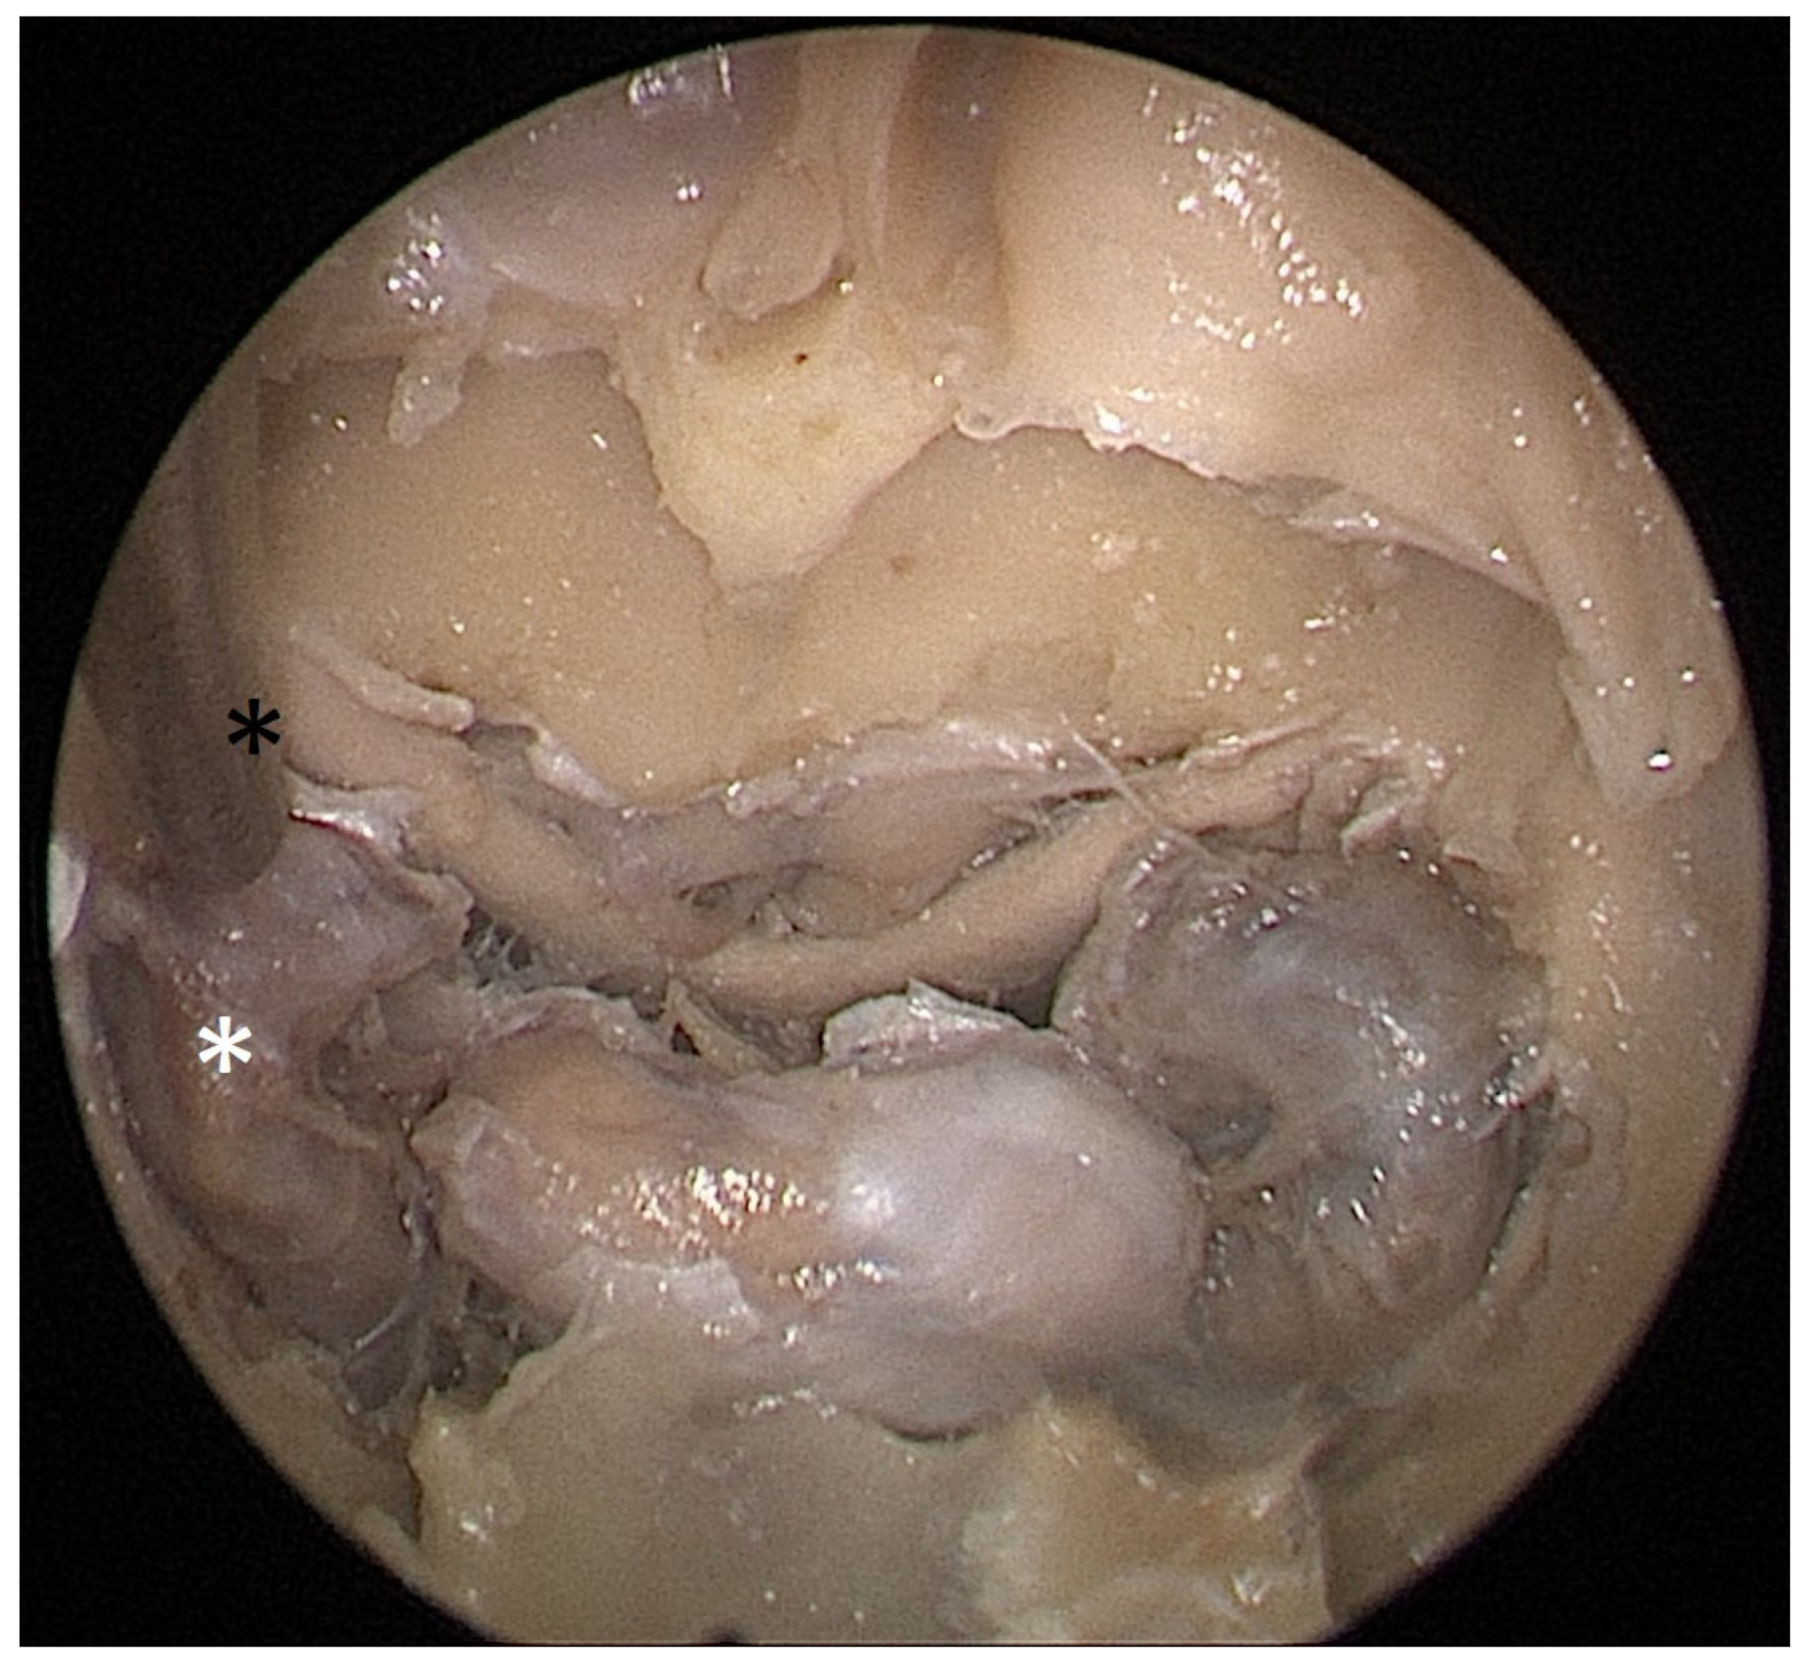

Cadaver pituitary surgery: On each of the two cadaveric heads, we used the paraseptal binostril approach for the sphenoid sinus. A 30° Storz endoscope (Karl-Storz, Austria, Vienna) was used. The head was mounted in a Mayfield cranial stabilization device. The surgery started with a lateralization of the inferior and medial turbinates. The anterior sphenoid wall and ostium to sphenoid sinus were identified. Using the straight suction with a marked scale, 1 cm and 2 cm distances from the anterior sphenoid wall were measured and marked with a scalpel on the posterior part of the septum. Using a scalpel, Kerrison punch, and backbiter punch, a posterior septal resection 1 cm from the anterior wall of the sphenoid was performed. We continued with the wide opening of the sphenoid cavity and resection of the intersphenoidal septum and the full exposure of the posterior wall, both ICAs, and optocarotic recesses (OCR). The posterior wall of the sphenoid sinus and dura were resected to better identify anatomic landmarks, with both ICAs, pituitary gland, chiasma, and optic nerves visible at the end of a resection (Figure 4). The straight suction was inserted into the sphenoid sinus so that the instrument’s tip was in the most lateral position in the sphenoid sinus without infracturing the rest of the nasal septum. A picture was taken in this position to evaluate the most lateral part of the sphenoid sinus that could be reached with a straight instrument with a 1 cm septal resection without infracturing the nasal septum (Figure 5). Enlargement of the septal resection to 2 cm from the anterior sphenoid wall was performed with a backbiter punch and scalpel. The straight suction was inserted into the sphenoid sinus so that the instrument’s tip was in the most lateral position in the sphenoid sinus without infracturing the rest of the nasal septum. A picture was taken in this position to evaluate the most lateral part of the sphenoid sinus that could be reached with a straight instrument, with a 2 cm septal resection, without infracturing the nasal septum (Figure 6).

Figure 4. Opened sphenoidal sinus, endoscopic view, fully exposed ICAs (white asterisks), pituitary gland (black and white star), and optical chiasm (black arrow).